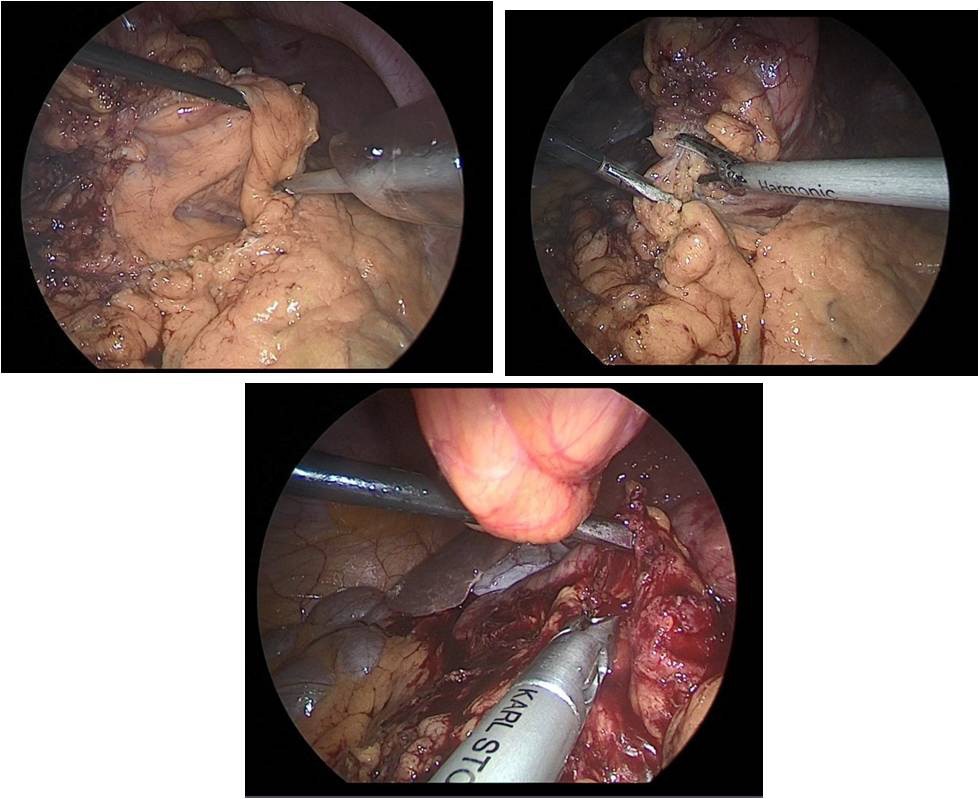

After crossing the pyloric sphincter, laparoscopic lymph node dissection of the VII, VIIIa, IX, XI, XIIa groups of lymph nodes was performed (Figure 9 a, b, c, d).

Then performed resection of the greater omentum with lymph dissection II, IV, VI groups of lymph nodes (Figure 10a,b).

Figure 9a,b,c,d: Lymph node dissection of the hilum of the liver and celiac trunk.

Figure 10a,b: Laparoscopic omentectomy.

Figure 11a,b: Laparoscopic omentectomy.